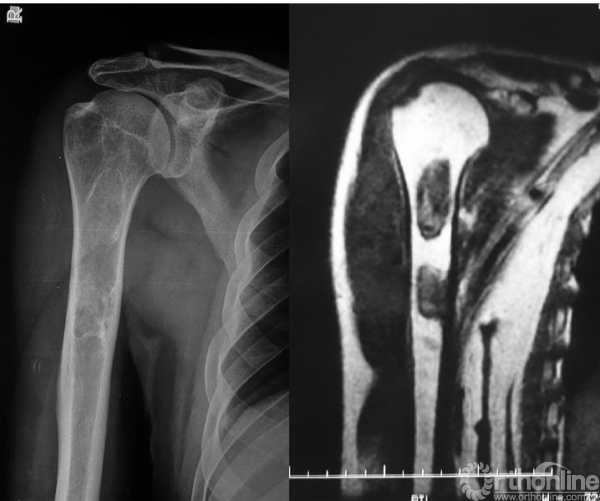

骨纤维异样增殖症可发生于任何骨骼,但四肢长骨为多,有单发也有多发,多位于长骨的干骺端,可局限或向骨干扩散,股骨的近远端、胫腓骨近端是最常见的部位,其次有肱骨、肋骨、锁骨、骨盆、脊椎骨、颌面骨等,多发型骨纤维异样增殖症常累及一侧肢体,偶尔也可双侧发病。

(2)多发型:占骨纤维异样增殖症的30%,病变可侵犯全身多数骨骼,常偏于一侧肢体骨,常以中线为界,严重的可造成肢体短缩(图3),偶尔也有双侧生长(图4)。

图3 右侧骨盆、股骨、胫骨多发病变、畸形

图4 左右锁骨同时发病,左侧并病理性骨折